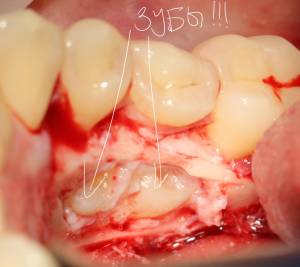

А вот они! Далее мы руководствуемся главным правилом хирурга-стоматолога:

При удалении зубов нельзя прилагать значительных физических усилий. Если операция идет правильно, зубы должны, вообще, сами вываливаться из лунок.

Однако, наши сверхкомплектные зубы вываливаться не хотят. Потому что их коронки образуют что-то вроде клина, который непросто вытащить через маленькое трепанационное отверстие.

Поэтому мы, всё также, с помощью ультразвука, отпиливаем коронку одного из зубов:

После чего, зубы вываливаются из лунок самостоятельно. В прямом смысле слова:

Вот удаленные зубы: